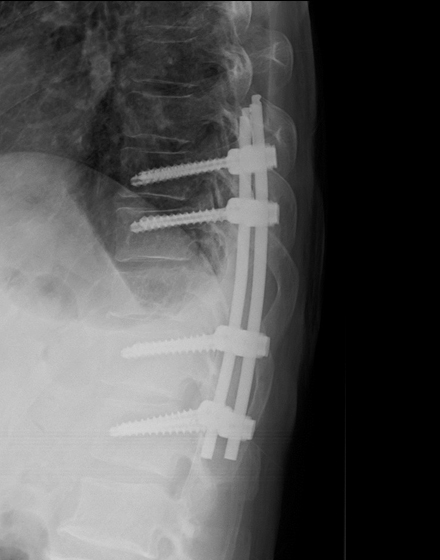

低侵襲経椎間孔的椎体間固定術 MIS-TLIF (エムアイエスティーリフ)

適応となる疾患:腰部脊柱管狭窄症、腰椎変性すべり症、腰椎分離すべり症など

従来の腰椎の後方除圧固定術は、背部に約10~15cm程度の切開を加え手術を行っておりましたが、当院では、皮膚切開を最小限に抑え(通常は約4~5cm程度の創)神経除圧と椎間板切除、人工骨の充填を行います。その後、約2cmの皮膚切開を別に2カ所ほど加えて、レントゲンを見ながら金属スクリューを安全に刺入します。この手術の利点は、筋肉の損傷を最小限にして、出血量低減、術後疼痛の軽減、早期離床、早期退院、早期社会復帰を可能とすることです。手術は2時間から3時間ぐらいで、翌日から起立、歩行が許可されます。入院期間は通常14日間程度になります。